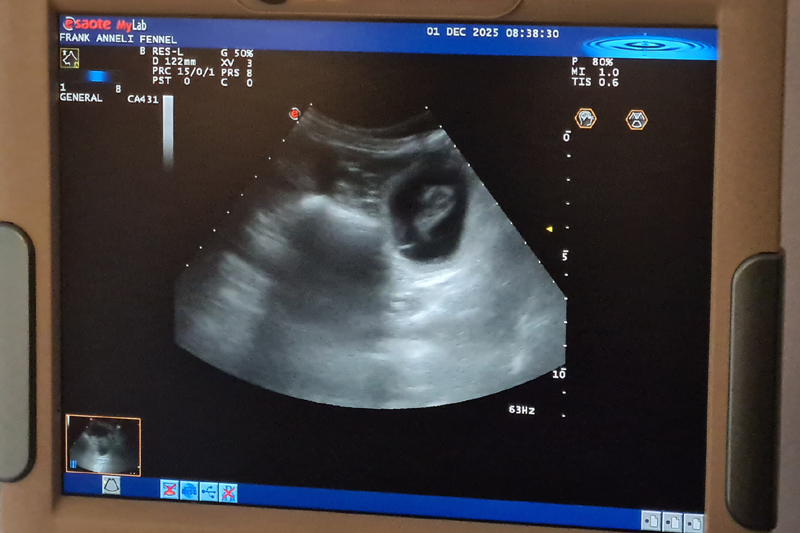

Ultraljud på måndag

På måndag gör vi ultraljud för att se om Fanny har valpar i magen. Håll tummarna!

Inga valpar....

Fennel är tyvärr inte dräktig. Vi har tyvärr haft otur igen med fryst sperma. Det är så trist för det finns så många fantastiska hanar där ute i världen

som jag så gärna vill ha i min avel. Men vi ger inte upp så lätt!